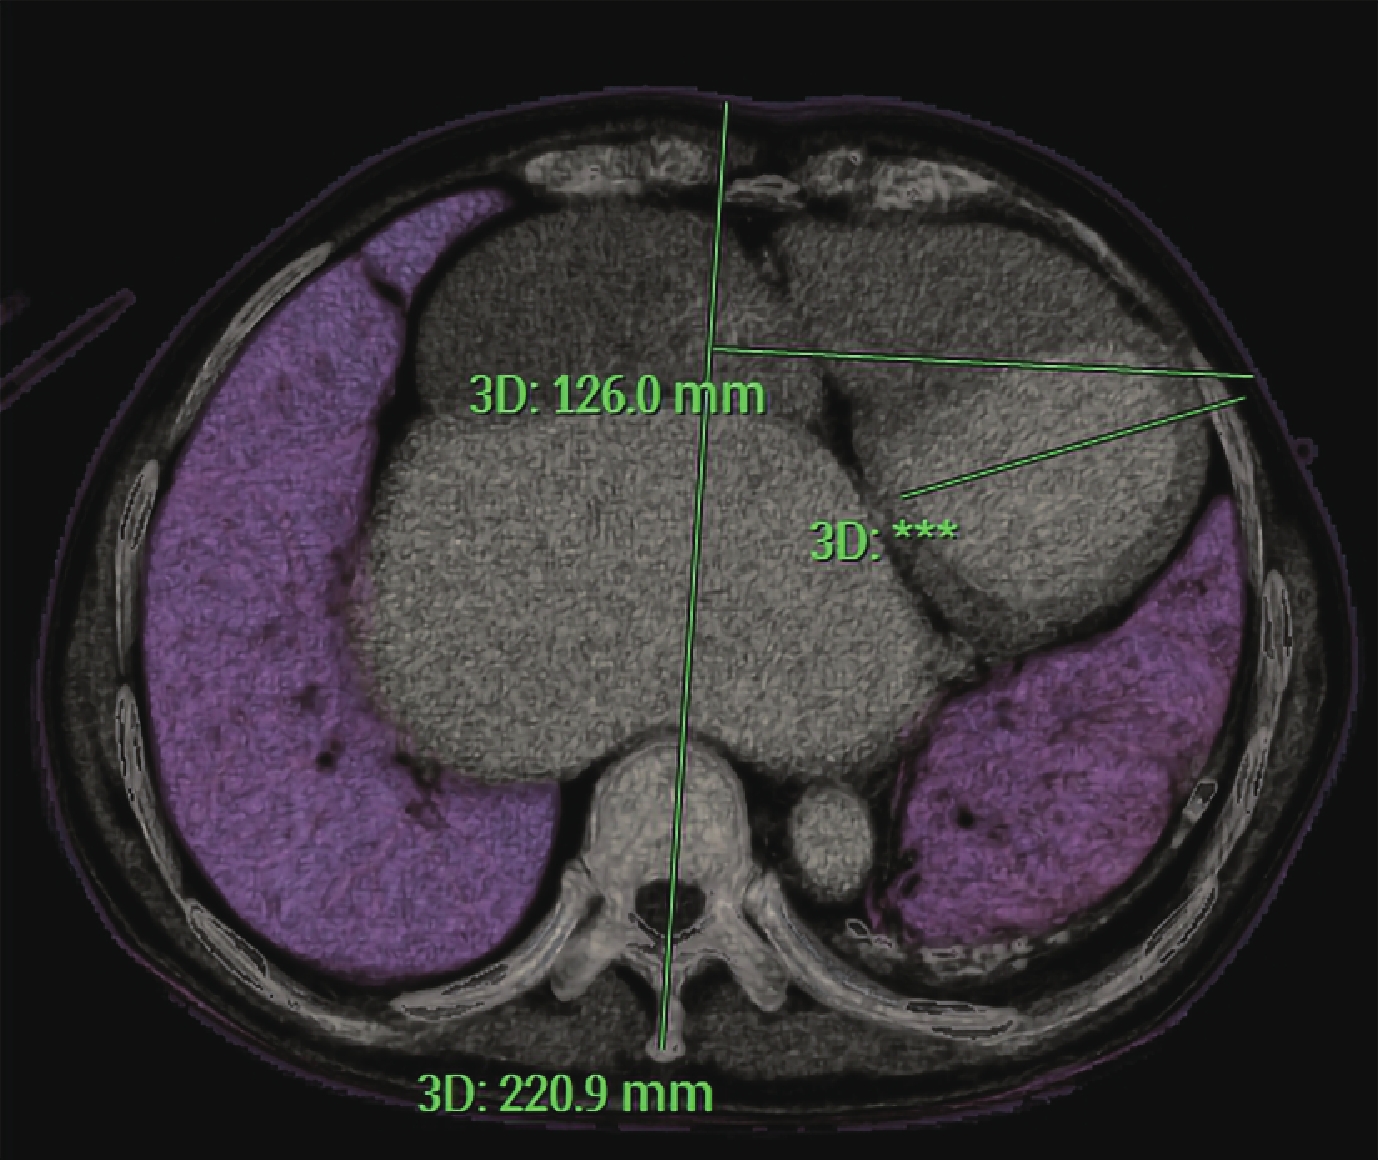

9 例患者術前均行 3D-CTA,重建要求對肋骨、心肌、主要冠狀動脈、左心室心腔、瓣周漏結構和肺組織等進行刻畫,明確上述各組織的空間位置關系,以及吸氣相肺組織與左心的重疊位置。心尖穿刺區域需避開主要冠狀動脈分支、肺組織、乳頭肌等。以該心尖穿刺點和“病灶處理區”(如瓣周漏處)為兩個端點,形成一條三維空間中的模擬連線(圖 1)。該連線在不通過肺組織的前提下向外延長至體表某一肋間隙,與體表相交點為體表穿刺點。找到該體表穿刺點所在的 CT 橫切面圖像,測量其與正中線的垂直距離(圖 2)。通過該肋間隙和上述距離即可幫助在體表確定穿刺位置。再次利用橫斷面顯示確認穿刺路徑不經過肺組織(圖 2)。